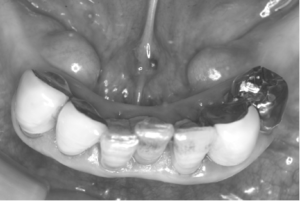

みなさんのお口の中を見たとき、歯茎の内側(舌側、口蓋)にぼこぼこっとこぶのようなものがある方はいませんか?

このこぶの正体は、“骨隆起”という骨の塊です。これは、顎の骨が過剰に発達することでできます。

骨隆起は、長年にわたり少しずつ大きくなります。そのため、気付いた時にはこぶが!!とびっくりする方もいます。

骨隆起自体は骨の上に薄い粘膜が一層覆っているだけなので、入れ歯を入れていると、骨隆起と入れ歯があたって痛みがあるなどの症状がでてきます。